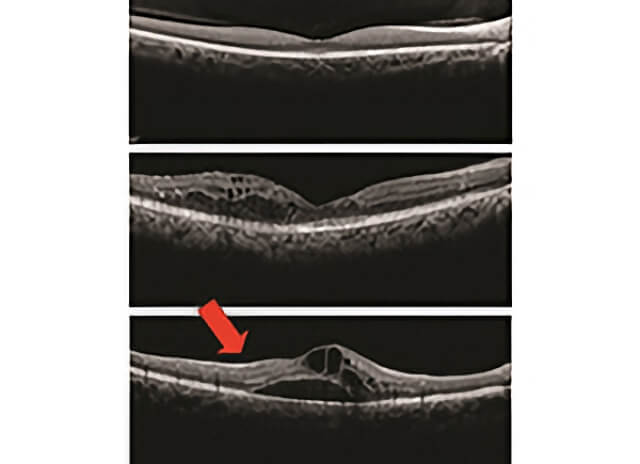

Optical Coherence Tomography and Macular Edema (Images courtesy of the ASRS Retina Image Bank, contributed by Dr. Suber Huang) OCT is a useful test to study macular edema (ME). • The top image is normal. Note the even layers and gently sloping dip of the macula called the fovea. This eye has excellent vision. • The middle OCT has ME, black-appearing cysts (arrows) which threaten the normal fovea. This eye also has good vision. • The bottom OCT shows ME involving the macula. Because ME involves the macular center (the fovea), vision is poor (large red arrow).